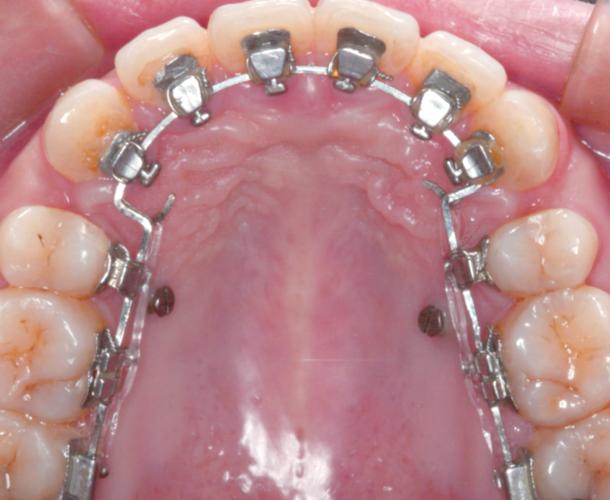

正畸方形勾托槽是口腔正畸治疗中常用的固定矫治器核心组件,其设计融合了力学原理与临床需求,通过精准传递矫治力引导牙齿向理想位置移动,与传统圆形托槽相比,方形勾托槽的核心特征在于“方形槽沟”与“勾状结构”的协同作用:基底多为金属(如不锈钢)或陶瓷材质,经酸蚀处理以增强与牙面的粘接固位力;槽沟呈标准方形,内径与方形弓丝(如镍钛方丝、不锈钢方丝)精准匹配,形成“面面接触”的嵌合关系;翼部设有结扎翼,便于医生用结扎丝或弹性圈固定弓丝;槽沟两侧或底部则设计有“勾”,辅助防止弓丝滑脱,增强稳定性,这种结构使其在复杂牙齿移动中展现出独特优势。

方形勾托槽的核心优势在于高精度的三维控制能力,方形槽沟通过限制弓丝在槽沟内的旋转和倾斜,使矫治力能够精准作用于牙齿的近远中、垂直向及颊舌向三个维度,在矫正牙齿扭转时,方形弓丝嵌入槽沟后,可通过“旋转加力”直接调整牙冠方向;在压低前牙或伸长后牙时,槽沟的方形结构能避免弓丝发生“颊舌向摆动”,确保力量垂直传递,部分方形勾托槽搭配低摩擦材料(如陶瓷滑道)或自锁设计,可减少弓丝与托槽间的摩擦力,降低牙齿移动阻力,缩短治疗周期,尤其适用于中重度拥挤、深覆合、深覆盖等复杂病例。

在临床应用中,方形勾托槽的适用范围广泛,青少年恒牙列早期矫治中,可用于解决牙列拥挤(通过扩弓或邻面去解除拥挤)、牙齿异位萌出等问题;成人正畸中,则能满足对牙齿转矩、轴倾度的精细调整需求,如改善“露龈笑”时需压低上前牙、纠正骨性畸形导致的牙齿代偿等,对于追求美观的患者,还可选择陶瓷材质方形托槽,其颜色接近牙齿,减少“钢牙” appearance,提升治疗依从性。